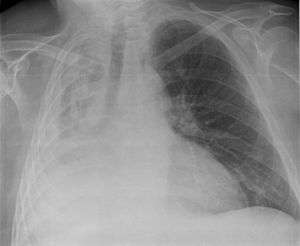

Atelectasis of the right lower lobe seen on chest X-ray

Post-surgical atelectasis will be bibasal in pattern.